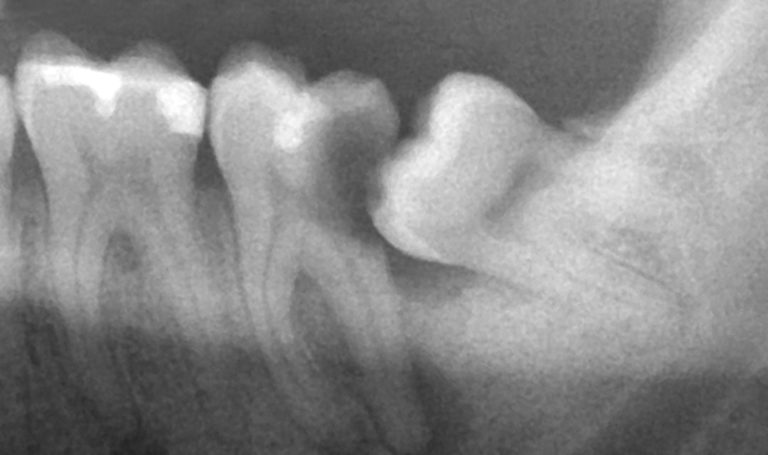

Экстракция зуба мудрости показана в том случае, если он находится в положении, при котором прорезывание невозможно. Это подтверждается рентгенологическим исследованием, удаление зуба проводят после снятия острых симптомов перикоронарита, после экстракции лунка зуба очищается, и накладываются швы. Назначают консервативную противовоспалительную и антибактериальную терапию.